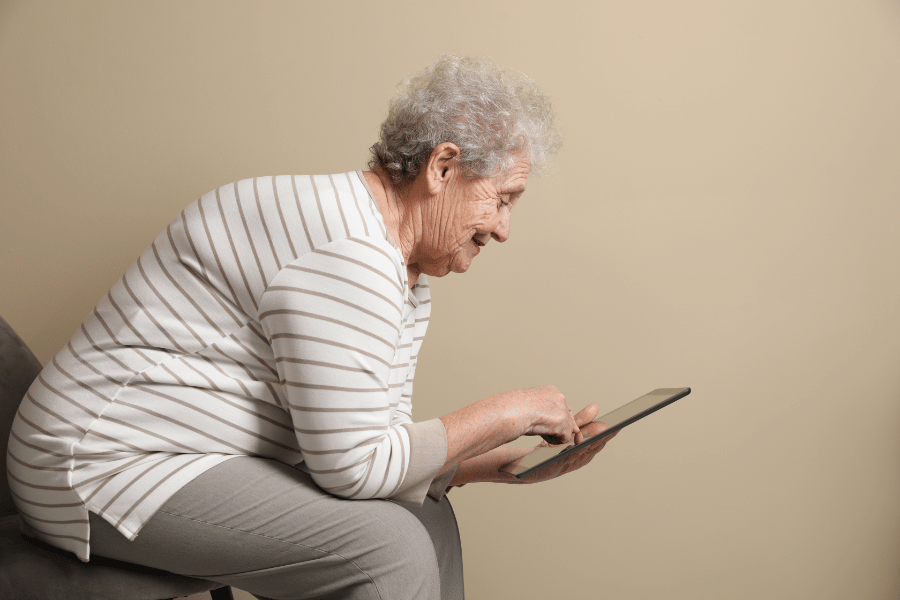

Z ustrezno ergonomijo položajev, kjer preživimo veliko časa, lahko precej zmanjšamo enostranske obremenitve hrbtenice – npr. med sedenjem za delovno mizo, pri stoji in drugih gibih, ki jih pogosto izvajamo v vsakodnevnem življenju. Človeško telo je narejeno za gibanje in dolge ure sedenja nam prav gotovo ne delajo nobene usluge, kjer so kolki konstantno v upognjenem položaju, hrbtenica pogosto usločena, glava pa potisnjena naprej, kar povzroča stalen stres na medvretenčne diske in fasetne sklepe. Z ustrezno ergonomijo, pogostim spreminjanjem položajev in pogostimi odmori z gibanjem lahko bistveno zmanjšamo obremenitve na hrbtenico.

Postavitev diagnoze se začne z izčrpnim pogovorom – kdaj so se težave pojavile, kakšni so znaki, kakšen je vaš življenjski stil, koliko in na kakšen način se gibate, itd. Spondiloza je sicer najpogostejša pri starejši populaciji, vendar se lahko pojavi tudi pri mlajših osebah, ki so redno izvajale določene aktivnosti, npr. ponavljajoče obremenitve hrbtenice (kompresije, iztegi, rotacije) in v primeru predhodnih poškodb.